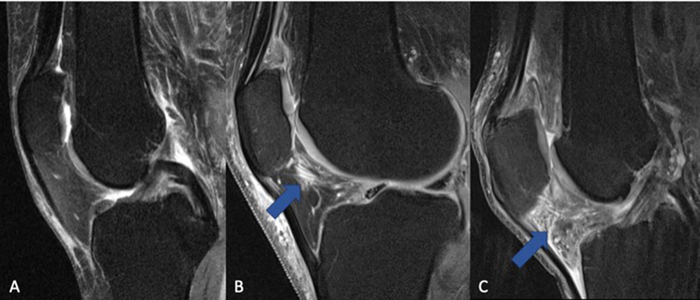

For the study, 277 participants from the Osteoarthritis Initiative cohort with moderate to severe osteoarthritis and sustained NSAID treatment for at least one year between baseline and four-year follow-up were included in the study and compared with a group of 793 control participants who were not treated with NSAIDs. All participants underwent 3T MRI of the knee initially and after four years. Images were scored for biomarkers of inflammation.

Cartilage thickness, composition and other MRI measurements served as noninvasive biomarkers for evaluating arthritis progression.